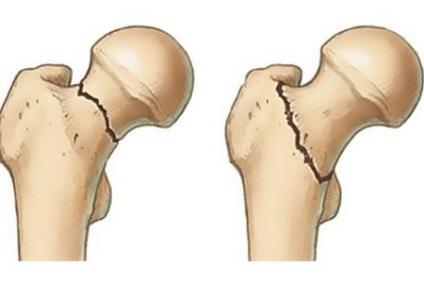

Boot a combnyaktörés egy protézis cikk (zárójel) hasonlító csomagtartó, hogy használják a konzervatív kezelés az ilyen típusú sérülés. Kívül a boot a sarok régiónak van egy keresztrúd, amely korlátozza az elmozdulás a lába körül a hosszanti tengelye a combcsont (forgás), ha a beteg hanyatt. Emiatt a boot nevezik derotation ( „de” előtag azt jelenti, korlátozása vagy annak hiánya). Kár, hogy a méhnyak számla 25% -át a csípőtáji törések nem része az állapotát.

Ortopédiailábbeli használni minden törések a combcsontot, hogy a trauma tartják az egyik a súlyos sérülést. A legjobb, a gyógyulási idő az ilyen sérülések körülbelül 6 hónap. Az okok a csípőtáji törések:

A betegségek kezelésére a integritását a combnyak különösen fontos egymás mellé helyezése fragmentumaik, azok erős rögzítés, feltételeinek megteremtése a gyors gyógyulását. Gátolja az eljárást a fúziós fragmensei természeti tényezők meglévő a combnyak. Ezek a következők:

- Sekély nyaki területen, hogy megfeleljen töredékek.

- Ennek hiányában a csonthártya a combnyak régióban.

- Gyors kimosódás vérömleny belüli ízületi folyadékban.

Impaktált törés, amikor az egyik fragmenst belsejébe vezetett a második, amikor egy csípőtörés fordul elő, ha nem volt egy csepp a offset kifelé lábát. Gyorsan diagnózis felállításához is nehéz, mert a kis számú tüneteket. Van fájdalom az ágyék, amely nem zavarja a sétáló pár napig, amíg ellentmondás törés élek. Ezután a láb rövidülhet a comb, a láb mozog kifelé, lehetetlenné válik emelkedik lába a fekvő testhelyzetben.